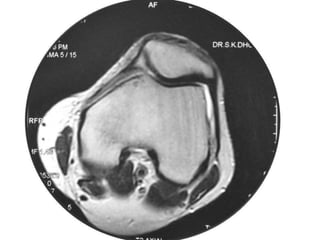

Osteoid Osteoma - MRI

• MRI has not been useful in the diagnosis of

osteoid osteoma.

• MRI is reserved for equivocal cases because it

can suggest the diagnosis of osteoid osteoma.

• MRI interpretation may result in errors in

diagnosis, most often confusion with

malignancies.

Osteoid Osteoma -MRI • MRI has not been useful in the diagnosis of osteoid osteoma. • MRI is reserved for equivocal cases because it can suggest the diagnosis of osteoid osteoma. • MRI interpretation may result in errors in diagnosis, most often confusion with malignancies.